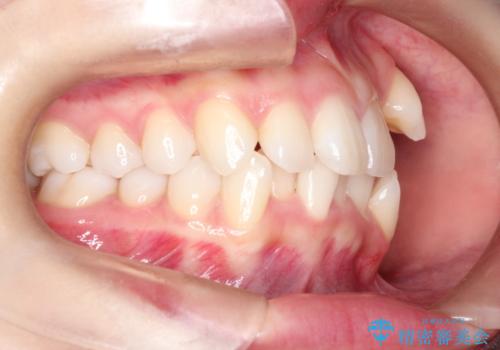

- 左上の犬歯の凸凹や正中のずれを主訴に来院されました。

凸凹を治すために、上下左右の小臼歯を抜歯してワイヤー矯正を行いました。

患者様には、顎間ゴムを使用していただくことで、2年という期間で治療を終了することができました。